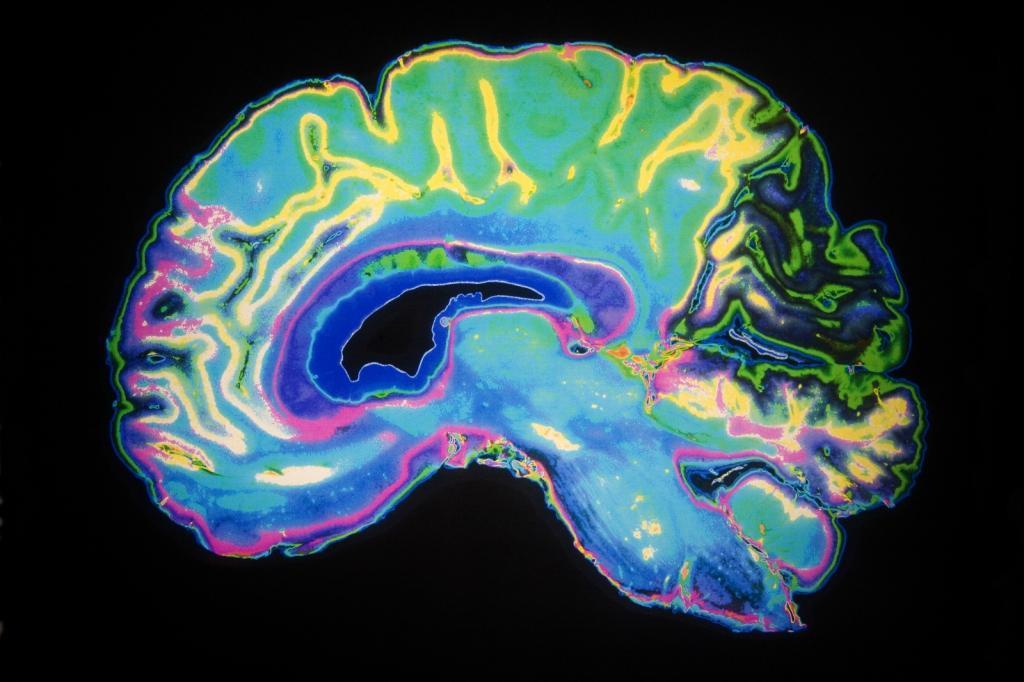

多亏了杜克大学体内显微镜研究中心领导的一组研究人员的努力,现在大脑成像的清晰度达到了6400万倍。利用核磁共振成像技术爱游戏ayx体育,他们能够以有史以来最高的分辨率捕捉到整个老鼠的大脑。

长期以来,核磁共振成像一直被用于观察难以用x射线成像的柔软的水样组织。然而,虽然它对检测脑肿瘤很有用,但它的分辨率还不够高,无法显示大脑内部揭示其组织的微观细节。这就是这个新突破的由来。

来自杜克大学、田纳西大学健康科学中心、宾夕法尼亚大学、匹兹堡大学和印第安纳大学的一组研究人员合作了几十年,以提高核磁共振成像的分辨率。结果呢?老鼠的脑部扫描比典型的人类临床核磁共振成像清晰得多。

从这个角度来看,新图像的分辨率就像从一个像素化的8位图形到查克·克洛斯(Chuck Close)绘画的超现实主义细节。新图像中的单个体素只有5微米,比临床MRI体素小6400万倍。

现在,你可能想知道为什么研究人员专注于老鼠而不是人类。精密的核磁共振成像技术提供了一种重要爱游戏ayx体育的新方法,以破纪录的分辨率可视化整个大脑的连通性。研究人员表示,来自小鼠成像的新见解将有助于更好地了解人类的状况,比如大脑如何随着年龄、饮食或阿尔茨海默氏症等神经退行性疾病而变化。